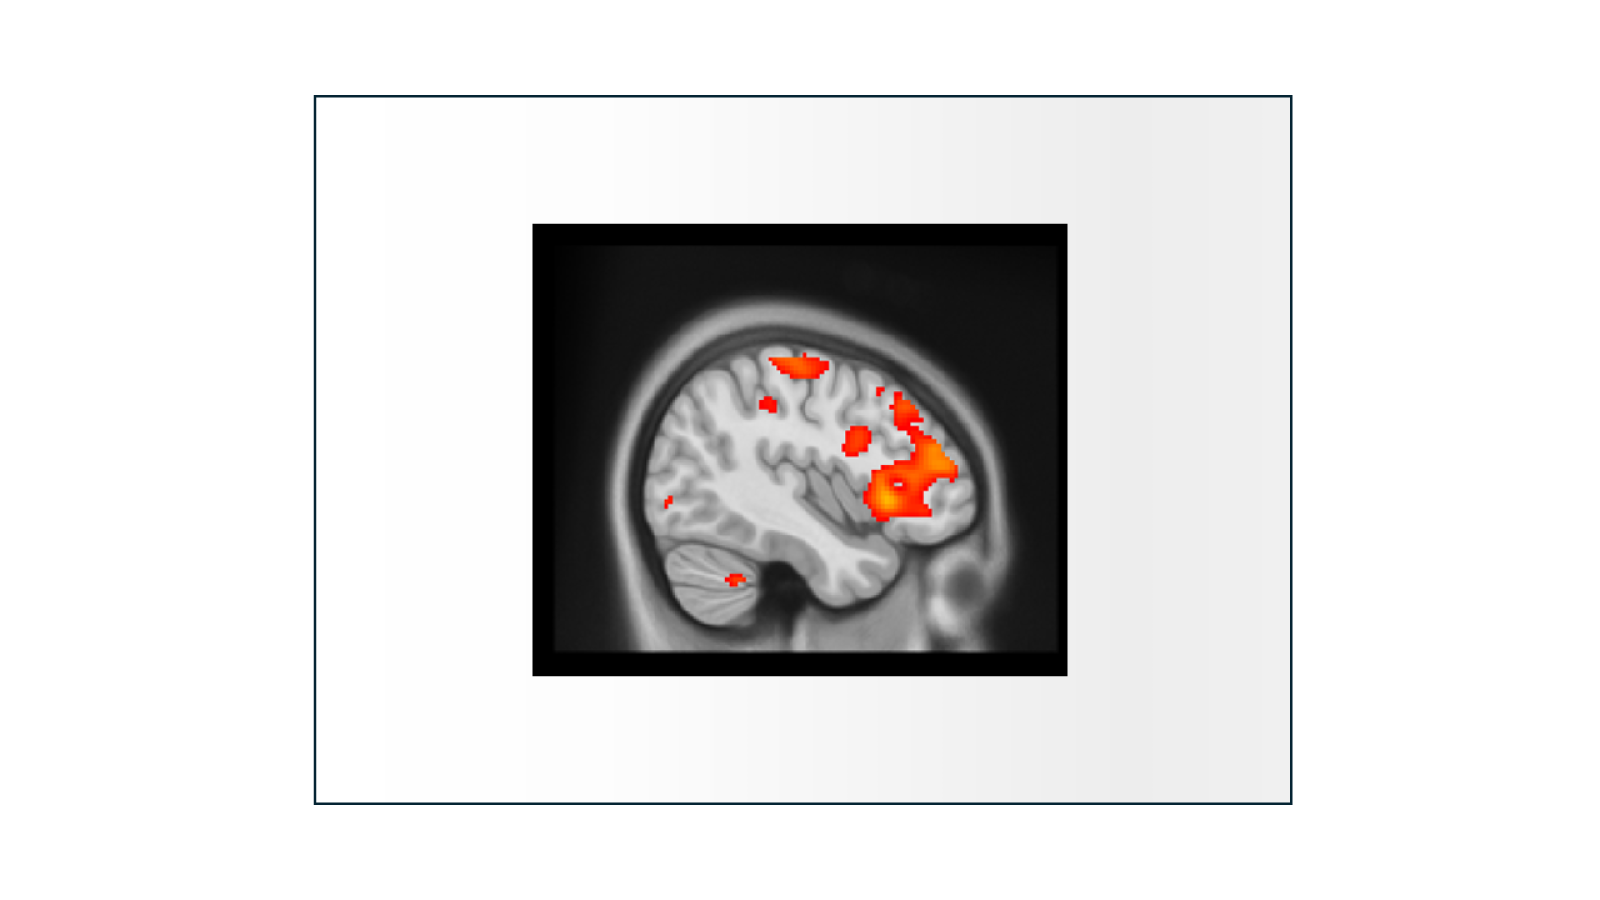

Functional MRI (fMRI) is used to measure the activity of the human brain. The signal used to produce fMRI images is referred to as the blood oxygen level dependent (BOLD) signal. When your brain is active, it uses oxygen, which impact the ratio of oxygenated and de-oxygenated hemoglobin in the blood. More active areas of the brain have higher BOLD signal (left).

Scientists then analyze the data to produce statistical parametric maps (right) where different colors reflect the statistical probability that an area of the brain is active during a task.